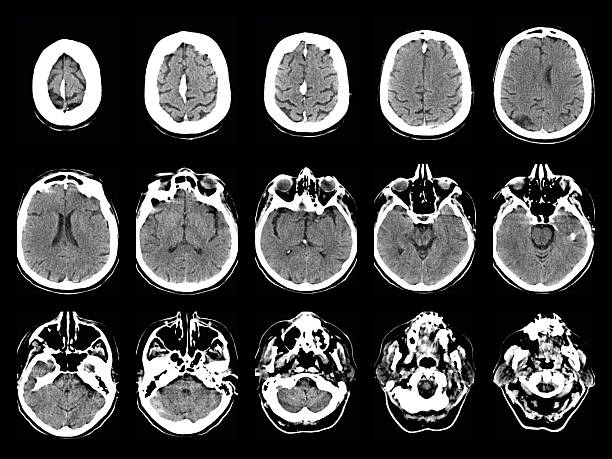

神經系統疾病,也稱為神經系統疾病或病癥,是影響中樞神經系統(大腦和脊髓)、周圍神經系統(大腦和脊髓以外的神經)或兩者的疾病。這些疾病是由神經系統的結構、功能或化學異常或功能障礙引起的。

- 中風:當流向大腦的血液被阻斷時,就會發生中風,從而損害大腦。它可能導致多種神經系統疾病,包括認知缺陷、言語問題和癱瘓。

- 正常壓力腦積水:在這種情況下,腦室會出現腦脊液異常積聚。這可能導致認知障礙、排尿失禁和行走困難等癥狀。